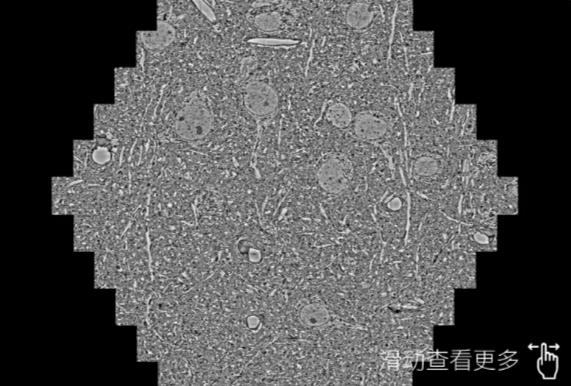

鼠脑切片。左图使用白银蔡司白银扫描电镜MultiSEM706对165μmx143pm面积区域成像,耗时仅需1.5秒。右图为鼠脑切片中30μm区域放大效果。样品由芝加哥大学B.Kasthuri提供。

使用蔡司高速白银扫描电镜MultiSEM对1mm²人脑皮层组织进行高分辨成像,并对其中的各种细胞结构进行三维重构分析。左图展示了2x3mm²组织平面中锥体神经元的三维重构效果。右图显示了局部体积神经元三维重构。图像由哈佛大学chtman实验室提供,渲染图由D. Berger 制作。